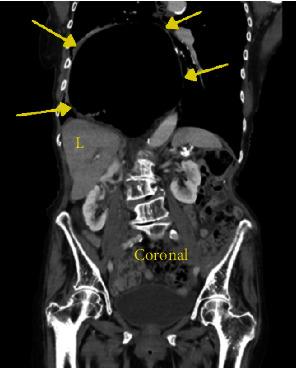

Hiatal hernia is a not uncommon anatomic disorder resulting in portions of the bowel occupying space in the thoracic cavity. There are a number of antecedent risk factors including obesity but not hiatal hernias resulting in symptoms. When symptoms do occur, they can include chest pain, nausea, abdominal pain, and gastroesophageal reflux. Cardiac arrhythmias have also been reported as associated conditions resulting from a hiatal hernia. To date, however, a complete heart block secondary to a hiatal hernia has not been reported. An 88-year-old female with a history of GERD (gastroesophageal reflux disease) was found to have a large hiatal hernia at endoscopy after she presented to the emergency department with nausea and abdominal pain. Prior to her scheduled surgical repair, she developed symptomatic third degree heart block which resolved with nasogastric tube deflation of the gastric contents. After surgical repair of the hiatal hernia, she developed episodes of atrial fibrillation with rapid ventricular response and was started on diltiazem. She eventually converted back to normal sinus rhythm and remained dysrhythmia free. In addition to other known arrhythmias associated with hiatal hernia, a complete heart block can also be seen. Acute management requires deflation of the chest occupying hernia. This appears to be the one of the first reported cases of complete heart block caused by hiatal hernia.

食管裂孔疝是一种较为常见的解剖学疾病,可导致部分肠管占据胸腔空间。有许多相关危险因素,包括肥胖,但食管裂孔疝并不一定会引发症状。当出现症状时,可能包括胸痛、恶心、腹痛和胃食管反流。心律失常也被报道为食管裂孔疝的相关病症。然而,迄今为止,尚未有因食管裂孔疝导致完全性心脏传导阻滞的报道。一名88岁有胃食管反流病病史的女性,因恶心和腹痛到急诊科就诊,在内镜检查时发现有巨大食管裂孔疝。在预定进行手术修复之前,她出现了有症状的三度心脏传导阻滞,通过鼻胃管排出胃内容物后得以缓解。食管裂孔疝手术修复后,她出现了伴有快速心室反应的房颤发作,并开始使用地尔硫䓬治疗。她最终恢复为正常窦性心律,且未再出现心律失常。除了与食管裂孔疝相关的其他已知心律失常外,还可见到完全性心脏传导阻滞。急性处理需要使占据胸腔的疝内容物排空。这似乎是首例报道的由食管裂孔疝引起的完全性心脏传导阻滞病例。